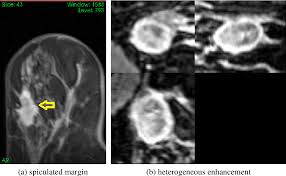

Can Ct Scan With Contrast Detect Breast Cancer - Breast Lumps Diagnosis Evaluation And Treatment : The cancer develops when abnormal cells crowd out healthy ones, potentially causing a lump in the breast or a bloody discharge from the nipples.. Breast cancer affects over 200,000 women each year. Luckily, i was still diagnosed pretty early. A ct scan is also called computerized axial tomography (cat) scan. In contrast with bone scans, which are only able to detect bone metastases, pet/ct has the advantage of concurrently imaging other common sites of breast cancer metastases such as the liver and lungs, says lead author patrick morris, a breast cancer specialist at memorial sloan kettering. This is an excellent way to take a needle biopsy for inflammatory breast cancer because imaging can show the best place to take the biopsy.

Learn the stage of your cancer. The term tomography comes from the greek words tomos (a cut, a slice, or a section) and graphein (to write or record). In contrast with bone scans, which are only able to detect bone metastases, pet/ct has the advantage of concurrently imaging other common sites of breast cancer metastases such as the liver and lungs, says lead author patrick morris, a breast cancer specialist at memorial sloan kettering. This is an excellent way to take a needle biopsy for inflammatory breast cancer because imaging can show the best place to take the biopsy. Ct scans are most often done as an outpatient procedure.

This test is most often used to look at the chest and/or belly (abdomen) to see if breast cancer has spread to other organs. Not necessarily is the whole body going to be scanned at that time. Once a nodule is found, a workup is done to see if it is cancer. If i had contrast on the earlier ct, my cancer would have been found 2 1/2 years earlier. Help check how well treatment is working and/or.